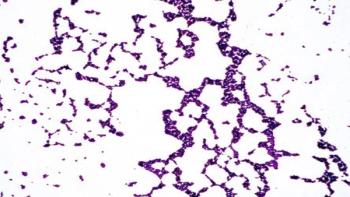

Previous research has shown that pairing antibiotics can be more effective than using single drugs, but finding these perfect matches has proven elusive. Researchers at University of Utah Health have developed a rapid screening method to identify beneficial pairs of existing FDA-approved drugs to combat multi-drug resistant (MDR) bacterial infections. The results are published online in PLoS Biology.